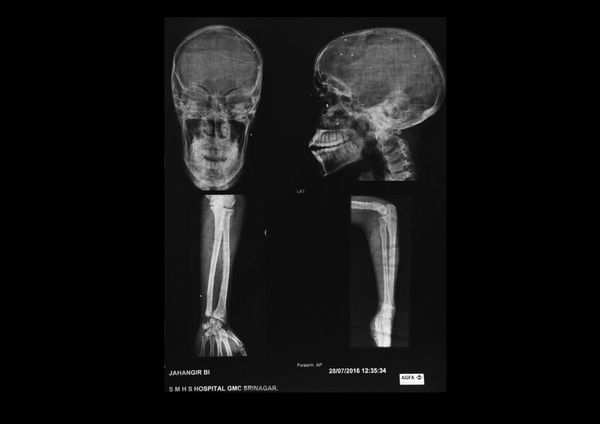

A visual investigation about the disastrous effects of the pellet guns used by the Indian army and the police forces in the Valley of Kashmir, India.

The valley of Kashmir, a territory disputed by India and Pakistan since 1947, is one of the most militarized zones in the world. In 2010 the Indian government provided the security forces deployed in the state of Jammu and Kashmir with a new weapon. Shotgun shells filled with hundreds of small lead pellets are since then used to keep urban protests under control. Defined as a “non-lethal” weapon, pellet guns should be aimed at the lower part of the body.

Hundreds of young boys filled the streets of Kashmir protesting against the “Indian occupation”, throwing stones against the army and the Kashmiri police. Security forces, since July 2016, responded using pellet guns extensively.

According to a UN report released in 2018, the new weapon is responsible for blinding around 1000 people and killing dozens.

Carrying dozens of pellets in their bodies, victims face unknown long term health consequences.